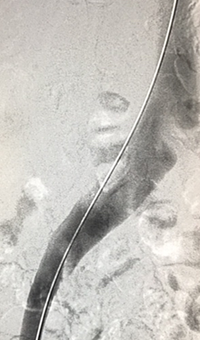

xray of femoral vein pre-treatment.

Femoral vein pre-treatment